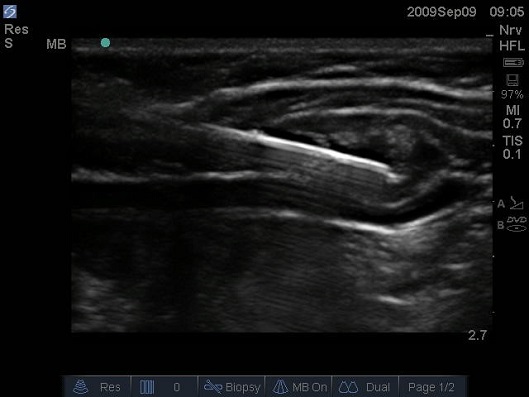

Figure 5 Ultrasound image of lateral abdominal wall of infant, needle inserted from anterior to posterior using an in plane needling technique. A 10MHz linear probe is positioned in the transverse plane midway between the iliac crest and costal margin.